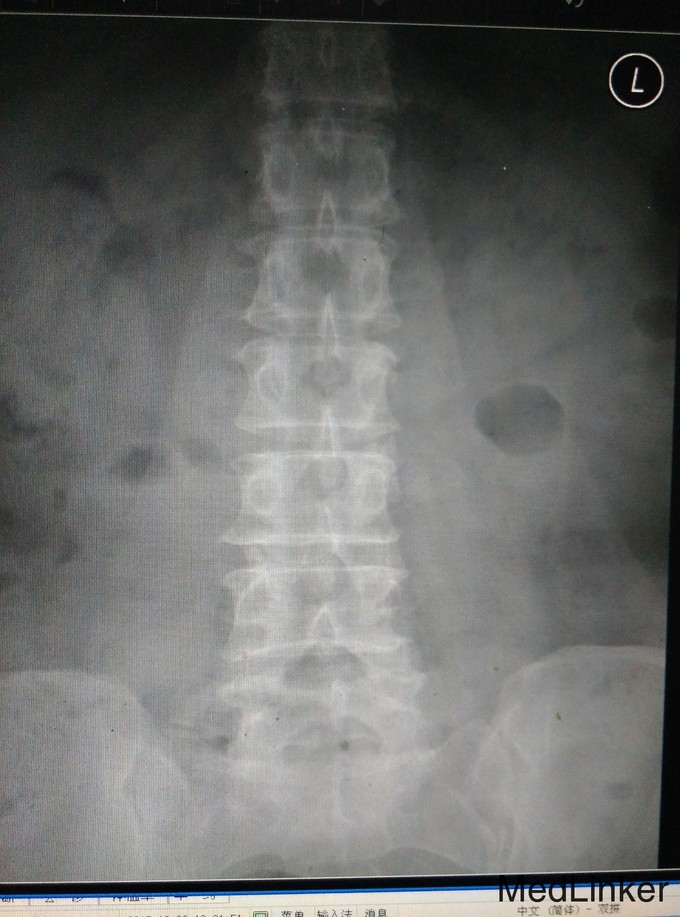

主诉:反复腰痛6年,加重伴双下肢麻木5个月。 病史:6年前无明显诱因出现反复发作腰部疼痛,无双下肢麻木及放射痛,劳累后加重,休息可缓解,5个月前出现上述症状加重,步行约300米后出现双下肢麻木乏力,休息后可继续行走,大小便正常。

查体:脊柱生理弯曲存在,无腰椎侧突畸形,腰4-骶1椎旁压痛和深部扣击痛(+),腰部活动稍受限,直腿抬高试验双侧阴性,双下肢浅感觉无明显减退,双下肢肌力4级,双下肢膝反射和踝反射稍减弱,髌阵挛、踝阵挛未引出。病理反射未引出,肛周浅感觉正常,肛门反射正常。 腰椎CT及腰椎MRI示:L4-5、L5-S1椎间盘突出,椎管狭窄,黄韧带肥厚,相应硬膜囊受压。